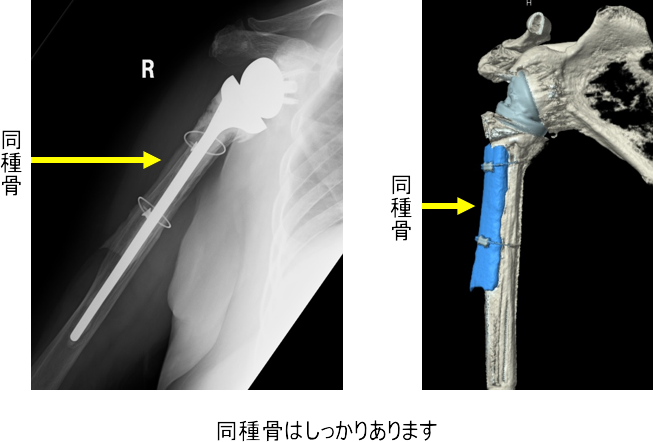

この方には、脛骨の同種骨を使用しました

同種骨をワイヤーで上腕骨に固定することで骨の割れ目がふさがるようにいたします。

術直後画像

同種骨は3年たっても上腕骨に固定され、ステムは上腕骨にしっかり固定されています